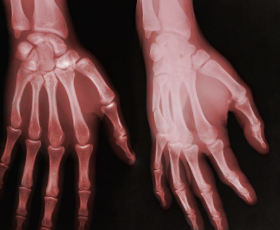

손가락 관절염 초기증상 원인 치료방법 등 정보에 대해 정리해드리도록 하겠습니다. 손가락 관절염은 손가락의 관절에 염증이 생겨 손가락의 움직임이 제한되는 질환입니다. 초기증상으로는 손가락 관절의 미세한 통증과 감각 이상이 나타날 수 있으며, 손가락을 움직일 때 뻣뻣함을 느낄 수 있습니다. 또한, 손가락 끝에 결절이 생길 수 있으며, 이러한 결절은 통증이나 감각 이상을 유발할 수 있습니다.

손가락 관절염의 초기 증상으로는 다음과 같은 증상이 나타날 수 있습니다.

- 손가락 관절의 통증: 손가락 관절 주위에 미세한 통증이 나타납니다.

- 뻣뻣함: 손가락을 움직일 때 뻣뻣한 느낌이 있습니다.

- 감각 이상: 손가락이 저린 느낌이나 쑤시는 느낌이 있습니다.

- 결절: 손가락 끝에 작은 결절이 생길 수 있습니다.

이러한 초기 증상이 나타나면, 증상이 악화되기 전에 전문의를 방문하여 진단을 받고 적절한 치료를 받는 것이 중요합니다. 손가락 관절염은 진행성이 있기 때문에 무시하면 손가락의 움직임이 점점 제한될 수 있습니다. 따라서 초기 증상에 대한 인식이 중요하며, 조기 발견과 치료가 중요합니다.